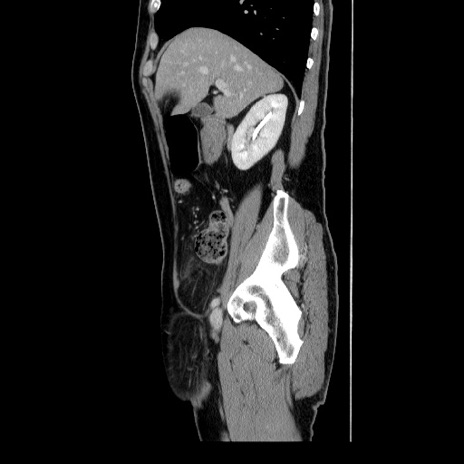

冠状断像

【症例】60歳代 男性

【主訴】右鼠径部膨隆

【現病歴】1年程前より右鼠径部膨隆あり。自己にて還納可能だったため放置していた。3時間前より右鼠径部の脱出を認め、還納困難となり受診。

【身体所見】右鼠径部に小児頭大の膨隆あり。弾性硬であり、用手還納は困難。左鼠径部にも膨隆を認める。脱出はなし。